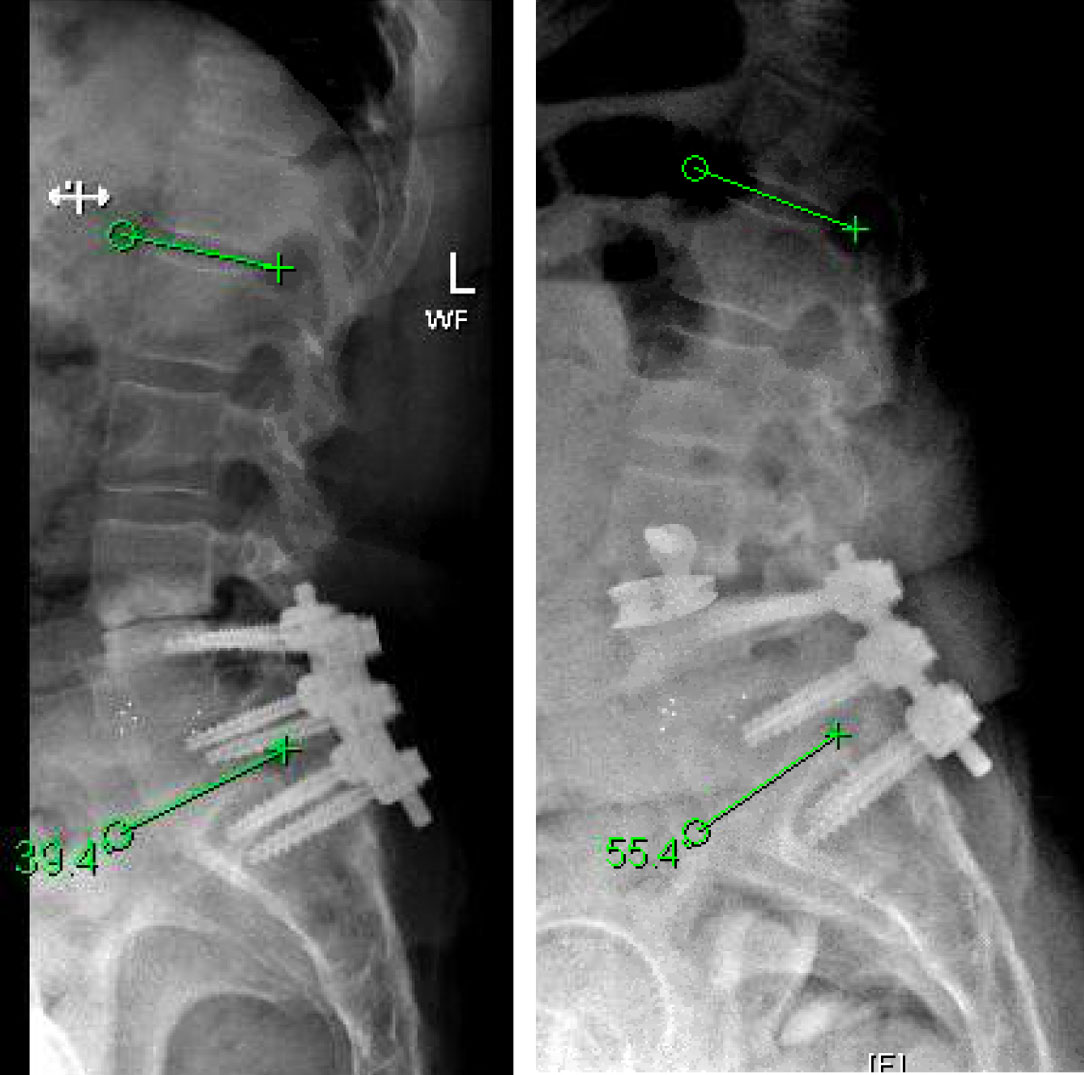

This is a 55 year-old-female who presented with progressively worsening axial low back pain and left lower extremity radiculopathy. She had a previous L4 to S1 posterior laminectomy with interbody fusion by another spine surgeon about three years prior. Imaging demonstrated L3-4 adjacent segment degeneration with spinal instability and stenosis. She additionally developed subsidence from her initial surgery, which resulted in loss of physiologic lordosis and presumptively accelerated the adjacent degenerative process. Her L4-S1 construct otherwise appeared to have a solid arthrodesis. Symptoms were debilitating and she had failed best medical management, therefore surgery was offered.

The goals of surgery were to achieve spinal stability, neural decompression, and re-establish a physiologic sagittal alignment. She had co-morbidities that precluded a more conventional open posterior approach with hardware revision. We therefore elected to perform an L3-4 Minimally Invasive Direct Lateral Interbody Fusion with Plate. This allowed for stability through the interbody device and lateral plate, indirect neural decompression by distracting the spinal canal and neuroforamina, and increase lordosis by lengthening the anterior aspect of the spine with placement of a hyperlordotic cage.

Patient tolerated the surgery well and attained near complete relief of her preoperative leg pain and chronic back pain. Incision was a little over one inch on her lateral side. Her postoperative pain was less significant given the indirect access to the spine which allowed for preservation of her paraspinal musculatures, and minimally invasive approach which maintained the integrity of the lateral muscle. She was discharged home on the day after surgery and was able to fully wean off her chronic narcotics.